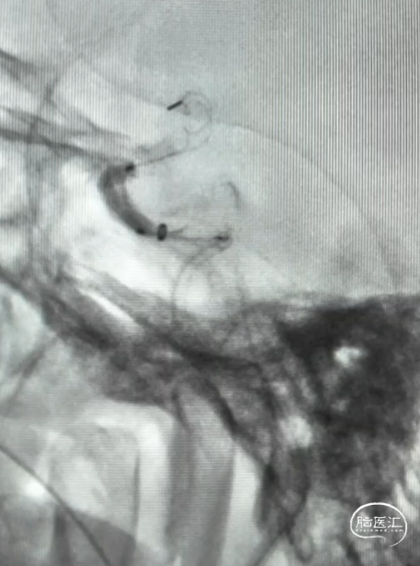

DCwire®微导丝通过闭塞段

微导管到达闭塞段以远真腔

释放4.0*30mm Syphonet®取栓支架

2.5*15mm SacSpeed®球囊扩张导管在C5段进行球囊扩张

2.5*15mm SacSpeed®球囊扩张导管在C1段进行球囊扩张

清理管腔血栓

回收4.0*30mm Syphonet®取栓支架

置入4.0*20mm 颅内支架

术后成形良好